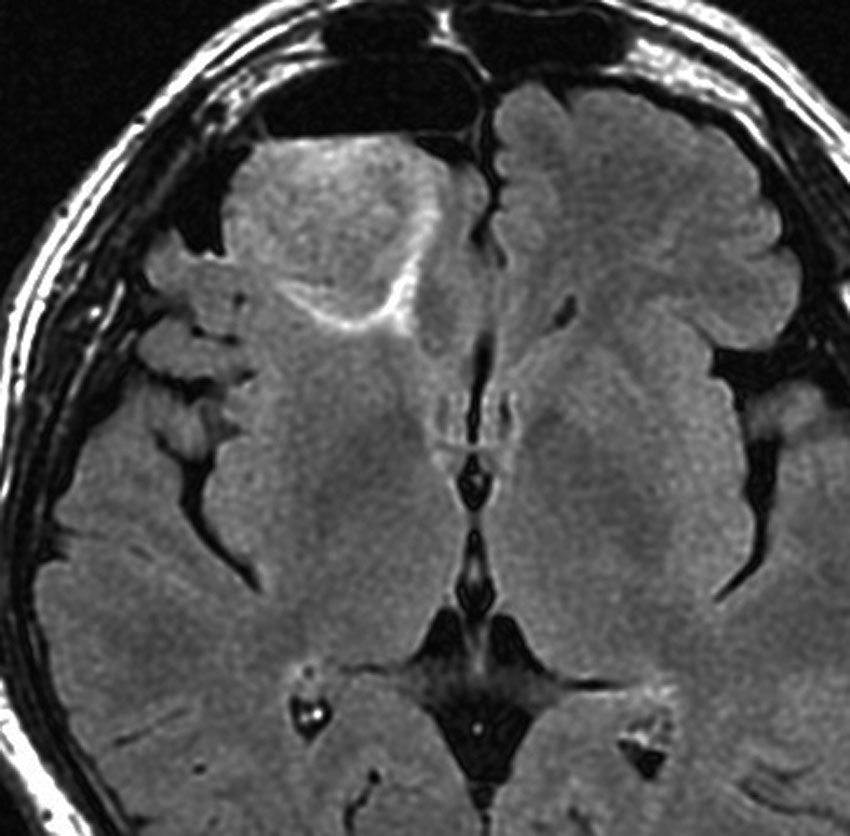

MRI画像ではびまん性星細胞腫と区別がつかないものがあります

左は脳ドックで発見された時のMRIです。壮年男性で無症状でしたので経過観察をしました。fronto-insulo-temporal gliomaと呼ばれる腫瘍で,びまん性星細胞腫と区別がつきません。右は無治療で6年後の画像です。ごくわずかに増大していますが,患者さんは相変わらず無症状で普通に働いています。このように数年間経過を見ても問題ない例もありますし,逆に数ヶ月で顕著な増大傾向を示すものもあります。発見されたらまずは,MRIを2ヶ月くらいで繰り返してどのくらいの速さで進行するかどうかをみるのが大切です。

平均的な増大速度を示した乏突起膠腫グレード2です。左が無症状で発見された時,右が3年後で,ごくわずかに増大しています。開頭手術で摘出しました。

左の画像は放射線治療直後のMRIですが,すでに腫瘍の縮小がみられます。

照射後7年の画像です。腫瘍は縮小したまま,患者さんは無症状で経過しています。